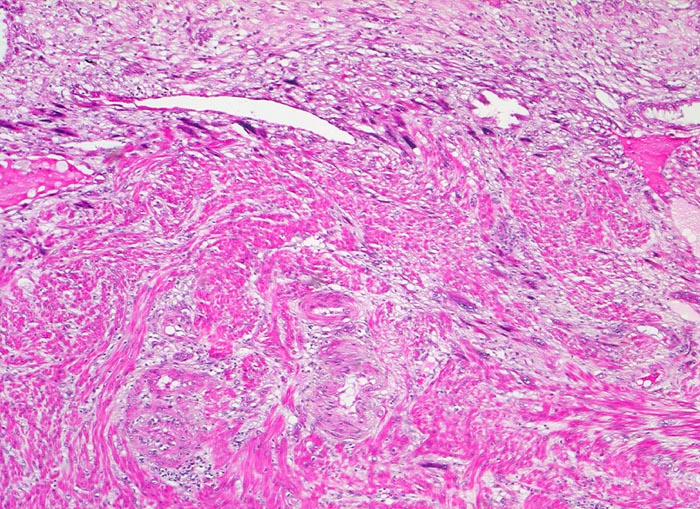

Gravidität

Extravillöser Trophoblast invadiert das Myometrium. Die Trophoblastzellen sind grösser als die glatten Muskelzellen des Myometriums und haben grosse hyperchromatische Kerne. Oben im Bild Anschnitt der Dezidua.

11. Schwangerschaftswoche. Normale Schwangerschaft

Als extravillöser Trophoblast werden die Trophoblastzellen der Haftzotten, der Trophoblastinseln zwischen den Zotten, des Chorion laeve und der Spiralarterien bezeichnet. Der villöse Zytotrophoblast findet sich ausschliesslich in Verbindung mit einer Basalmembran. Je weiter die Zellen des extravillösen Trophoblasten (=Intermediärtrophoblast) von der Basalmembran entfernt sind, um so mehr verlieren sie ihr Wachstumspotential und differenzieren zu Zellen mit invasiven Eigenschaften.